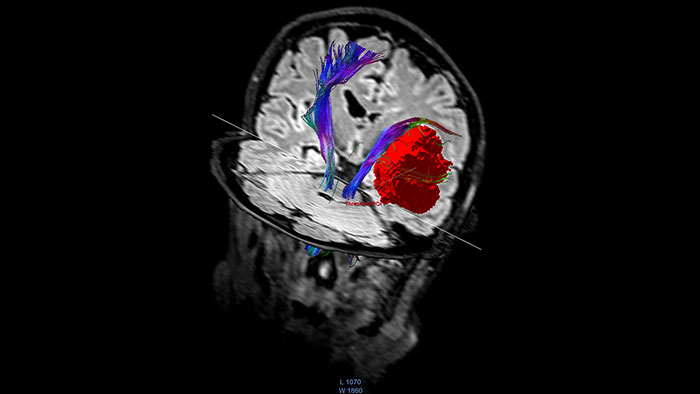

Visualize white matter connectivity in the brain

Provides visualization and quantification of white matter structure in the brain and spinal tracts using task guidance for generating common or user-defined tracts.

Benefits

• The guidance panel suggests which regions of interest and plane are common for identification of certain tracts such as the corticospinal tract.

• The results can be overlaid with other data like fMRI or anatomical series.

• Allows evaluation of fiber tracts around tumors and lesions in combination with functional areas.

• Supports DICOM-based output with merged anatomical tractography information through the Multi Modality Viewer.